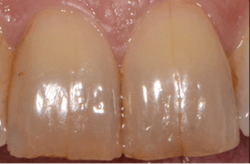

Craze lines

Craze lines are hairline fractures in the outer enamel of the tooth and presents as vertical lines commonly found in the front adult teeth. (See figure 1, courtesy of Spear Education, and also read How To Classify the 5 Types of Cracked Teeth.) They are very shallow and painless and usually cause no issues. Craze lines are more of a cosmetic issue, and depending on the size, may collect stain and plaque.

Craze lines are produced from years of wear and tear ranging from general use, prolonged clenching or grinding, eating hard foods such as popcorn kernels, or chewing ice. Other causes are trauma to the mouth, using teeth as tools, chewing on objects, nail biting, tongue rings, previous dental drillings on the tooth, and sudden extreme temperature changes like drinking something hot then following with something really cold. 1, 2

Treatment is not commonly needed, so the options are to leave it alone or possibly have a cosmetic restoration if it’s aesthetically bothersome. Craze lines can’t be removed entirely, so a veneer (a composite or porcelain material that covers the front of the tooth) may be recommended to cover them.